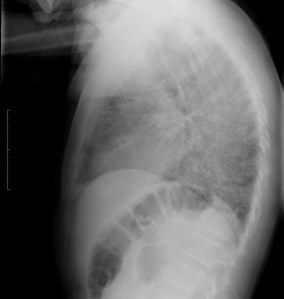

Se realiza placa de tórax, donde observamos:

Describamos los hallazgos:

Radiografía: Inespecífica, 90% patológicas. Hasta 15% normales. Opacidades focales o en vidrio deslustrado, Infiltrado reticular intesticial, Neumatoceles, distribución perihiliar frecuente.

TAC: Vidrio deslustrado difuso y perihiliar frecuente, infiiltrado reticular, consolidaxión y patrón de árbol en brote, engrosamiento de septos, patrón en empedrado, derrame pleural, quistes.